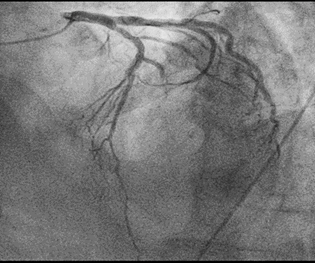

A ventriculography (Figure 4) was in LAO and RAO projections performed and revealed apical ballooning with preserved basal contraction function. This picture was showing a typical takotsubo cardiomyopathy.

Figure 4 Levocardiography.